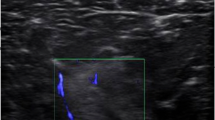

All ultrasound images were acquired by an expert operator (MVF) with the same ultrasound device throughout the whole study (Aixplorer Ultimate, SuperSonic Imagine, Aix-en-Provence, France) using a linear 50 mm transducer (SuperLinear SL18-5, SuperSonic Imagine, Aix-en-Provence, France). Participants were asked to lie prone on a massage bed and were instructed to rest with extended knee joints, and to relax completely during image acquisition with their feet placed just outside the bed frame in order to avoid any lower limb imbalances. Five minutes of rest in this position were provided for body fluid shift stabilization.

At each ROI, the transducer was placed on the lateral portion of the posterior thigh (just before the Biceps femoris long and short heads muscle borders) and then moved on the transversal plane in a lateral-to-medial fashion until the end of borders of the semimembranosus and the start of gracilis muscle were identified, then the panoramic acquisition was stopped. We have carefully ensured that the images were collected at the right angle in the transverse plane by using a plastic guide placed on the skin of the volunteer’s thigh, similar to the one used by Noorkoiv et colleagues13. The transducer was kept in contact with the guide throughout the whole acquisition of CSAs, thus we ensured that the right CSA path was followed while keeping the transducer perpendicular to the skin. The operator took meticulous care in keeping the pressure as constant as possible during the entire image acquisition. For all scans, transmission gel was used to improve the acoustic contact and to keep the pressure on the skin to a minimum. For the purpose of test–retest reliability assessment as outlined below, EFOV scans were acquired twice after completely removing the transducer from the skin and with 5 min rest period in between.